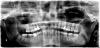

GBean Опубликовано 5 декабря, 2012 Поделиться Опубликовано 5 декабря, 2012 (изменено) Уважаемые врачи, нужна ваша консультация.Есть нижняя правая 8-ка. Она частично погружена в десну. Сейчас не беспокоит, но уже 2 раза за последние 3 года делали иссечение капюшона. Хочу от нее избавиться совсем.Врач, удалявший 2 другие 8-ки (на снимке одна еще стоит), увидев орто, сказал, что удалять только в стационаре.Что скажите вы?Если стационар, то где в Петербурге это можно сделать?Заранее спасибо,Женя.P.S. Есть КТ этой части челюсти - если разберусь как выложить и это нужно - выложу. Изменено 5 декабря, 2012 пользователем GBean Ссылка на комментарий

pawa Опубликовано 5 декабря, 2012 Поделиться Опубликовано 5 декабря, 2012 амбулаторно можно, но кт есть смысл посмотреть для определения соотношения корней с сосудисто-нервным пучком. Ссылка на комментарий